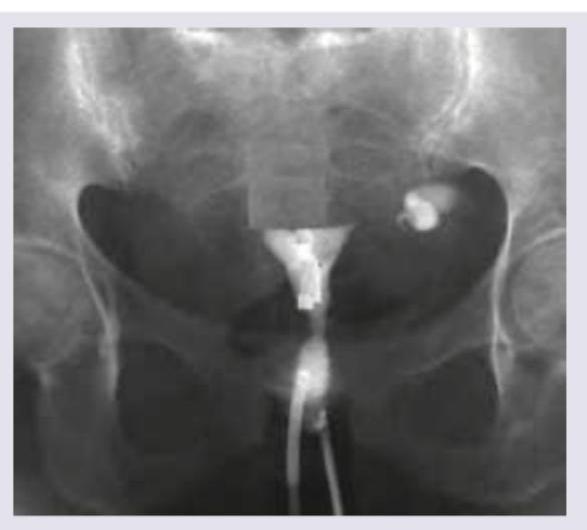

HSG image given below shows:

Explanation: ***Asherman syndrome*** - The HSG image shows multiple **filling defects** and an **irregular, partially obliterated endometrial cavity**, which are characteristic findings of Asherman syndrome. - This condition is caused by **intrauterine adhesions** (synechiae) resulting from trauma to the endometrial lining, typically due to procedures like D&C. *Endometrial polyp* - An endometrial polyp would typically appear as a **single, well-defined filling defect** within the endometrial cavity. - The image demonstrates **multiple, irregular adhesions** rather than a solitary, smooth-bordered mass. *Genital TB* - Genital tuberculosis can cause a variety of HSG findings, including **calcifications**, **beading of the fallopian tubes**, and a **"T-shaped" or constricted endometrial cavity**. - While it can cause intrauterine adhesions, the image's appearance of widespread, irregular filling defects with partial obliteration is more classic for Asherman syndrome, specifically if there is no other evidence of TB. *Subserosal fibroids* - Subserosal fibroids are located on the **outer surface of the uterus** and typically do not distort the endometrial cavity or appear as filling defects within it on an HSG. - On HSG, they may cause **extrinsic compression** or displacement of the uterus but would not appear as intraluminal filling defects or adhesions.